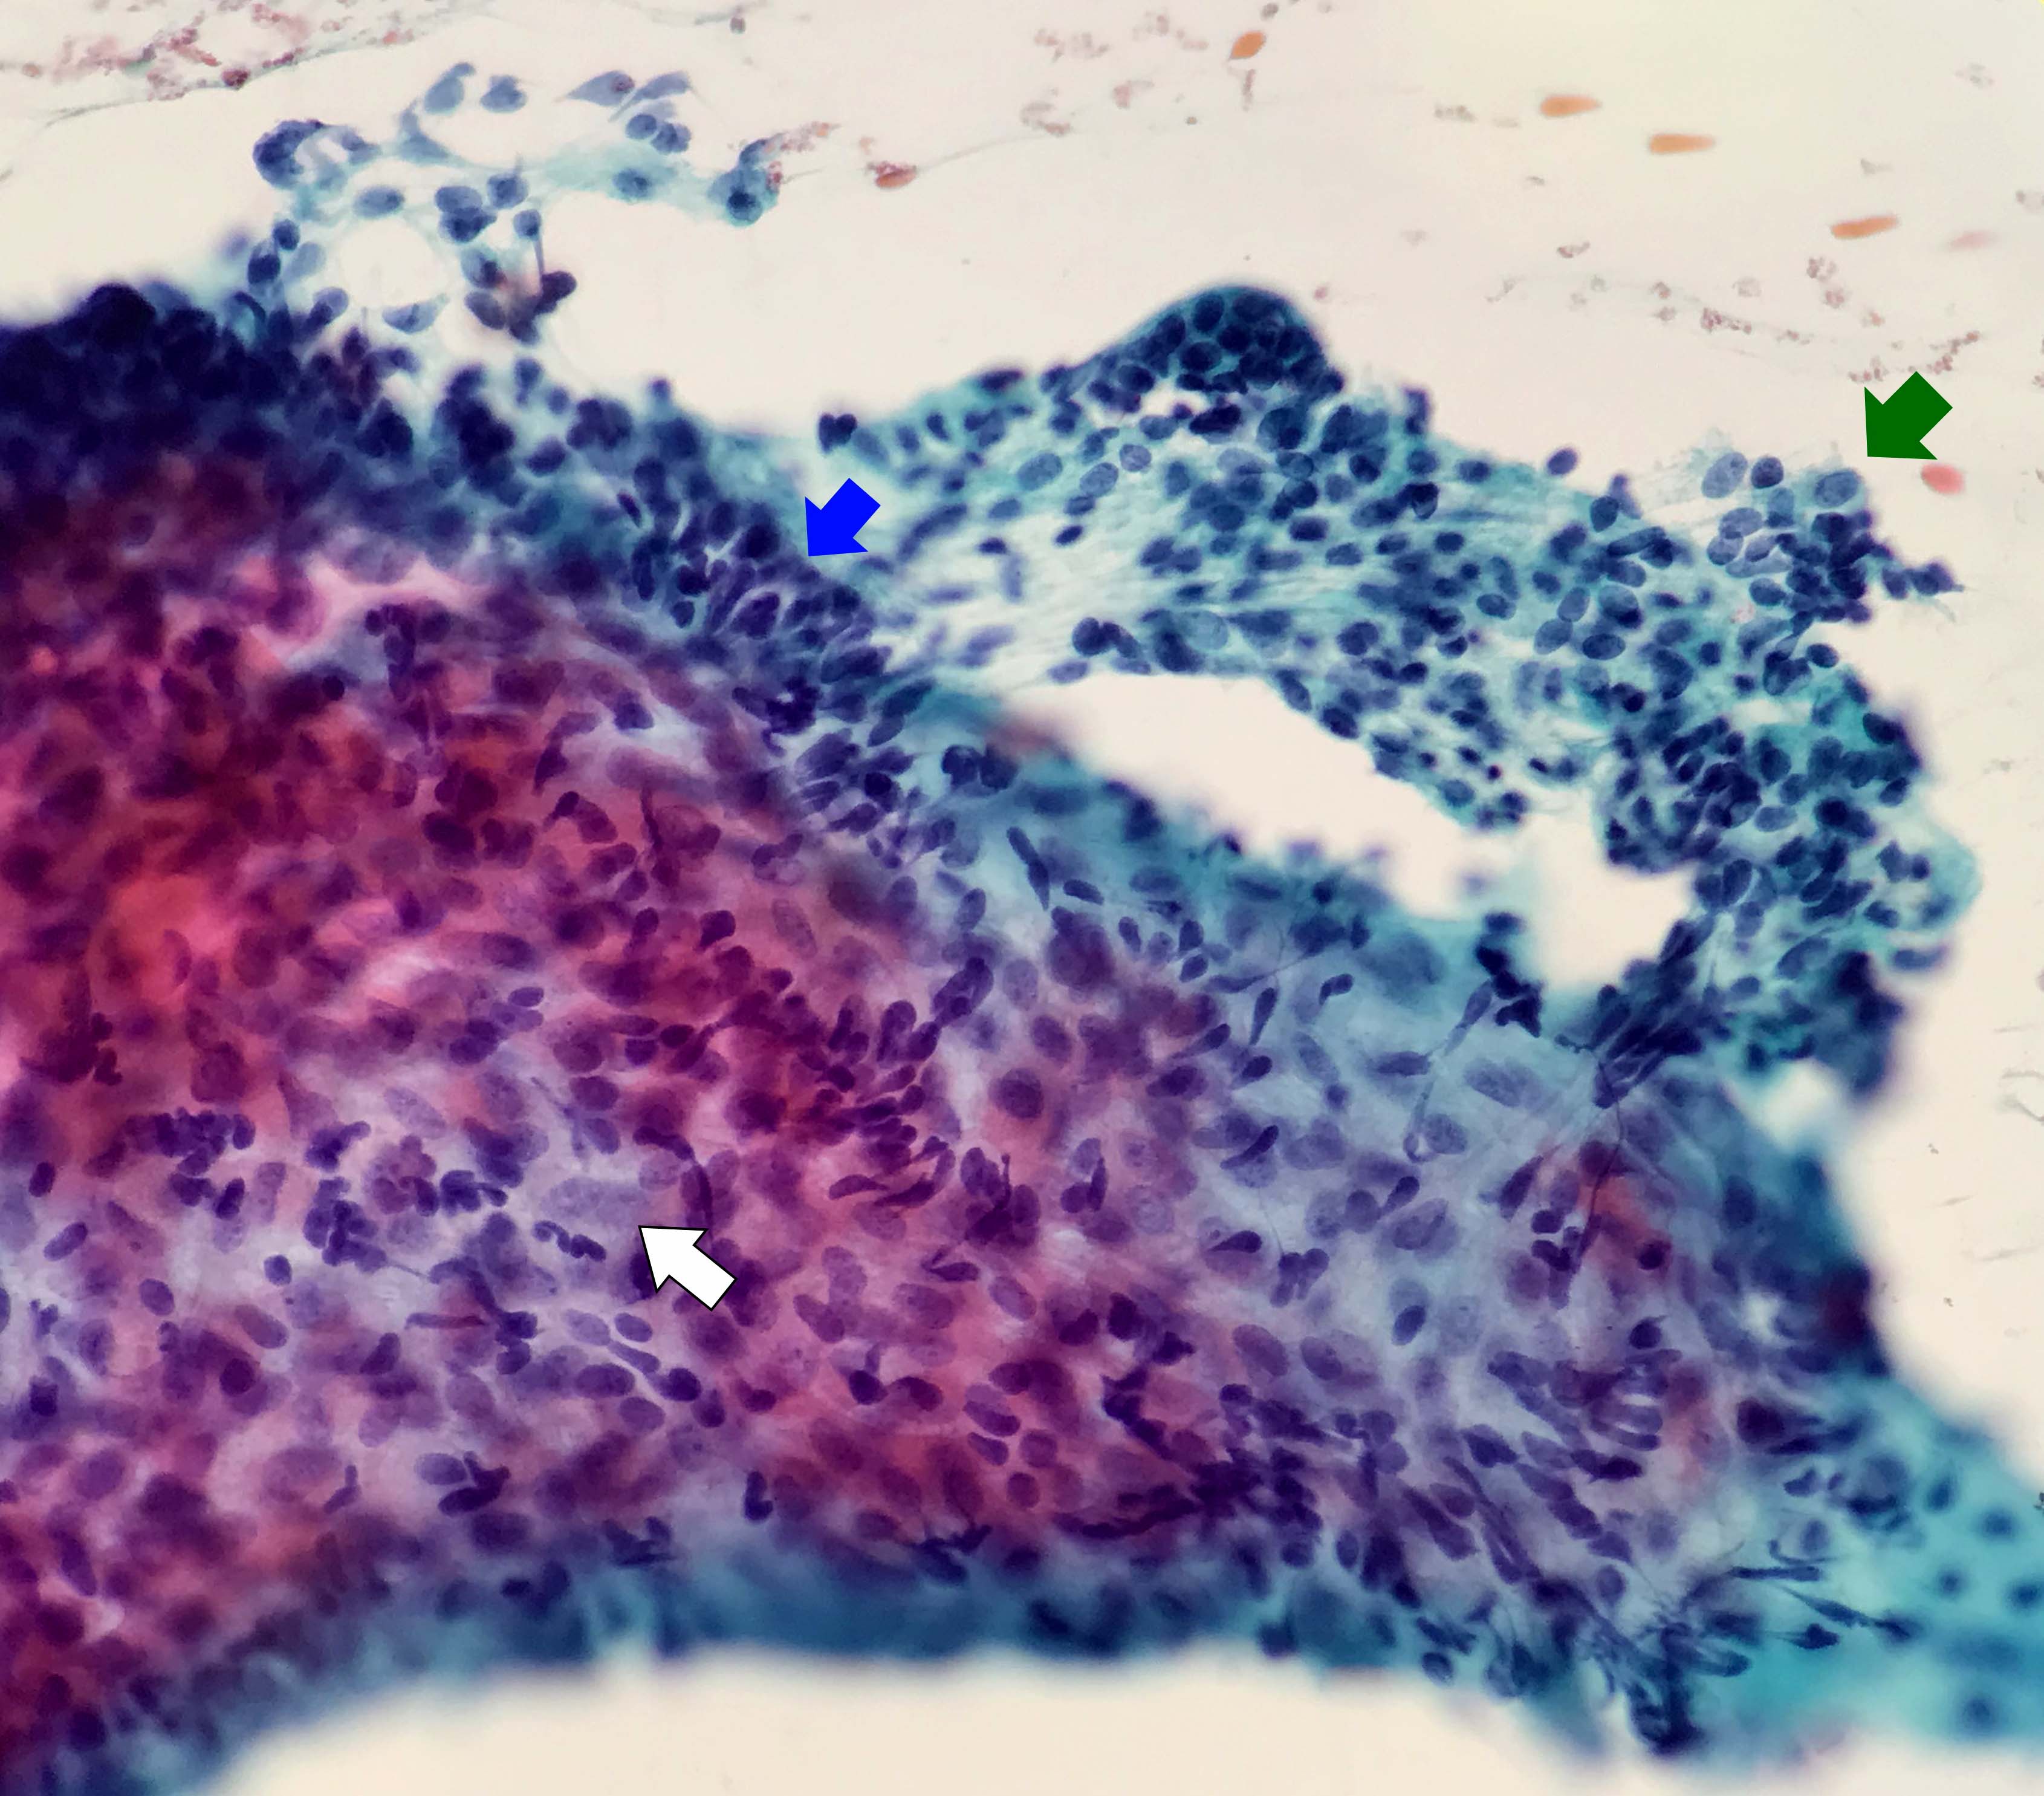

Contributed by Kelly Magliocca, D.D.S., M.P.H. and Anne C. McLean-Holden, D.M.D., M.S.

Cytology description

- Compact and cohesive cell clusters with areas of short branching of tumor cells along the periphery (Diagn Cytopathol 2013;41:206)

- Oval to round basaloid cells with high nuclear to cytoplasmic ratios, fine powdery chromatin, nucleoli with small peripheral nucleoli to inconspicuous nucleoli

- Squamous cells centrally with more abundant cytoplasm (particularly in acanthomatous variant)

- Possible limitations to FNA

- Inadequate sampling due to extensive cyst formation within the tumor

- Inability to distinguish ameloblastoma with macrocystic degeneration from ameloblastoma, unicystic type

- Inability to distinguish ameloblastoma from metastatic ameloblastoma without prior knowledge of metastatic disease

- Inability to distinguish ameloblastoma from other benign odontogenic tumors that are managed with curettage (e.g. adenomatoid odontogenic tumor, ameloblastic fibroma) (Diagn Cytopathol 2013;41:206)